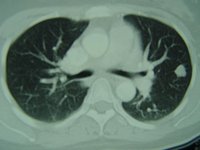

同樣,為了看清您同時拿著鳳梨和香蕉,您的朋友必須從兩個方向觀察您的影子,以獲得完整的意象。這就是計算機化軸向斷層掃描的基本概念。在CT掃瞄器中,X光束圍繞著患者的身體進行運動,從數百個角度進行掃描。計算機負責收集所有信息,並將這些信息合成為人體三維圖像。

CT掃描